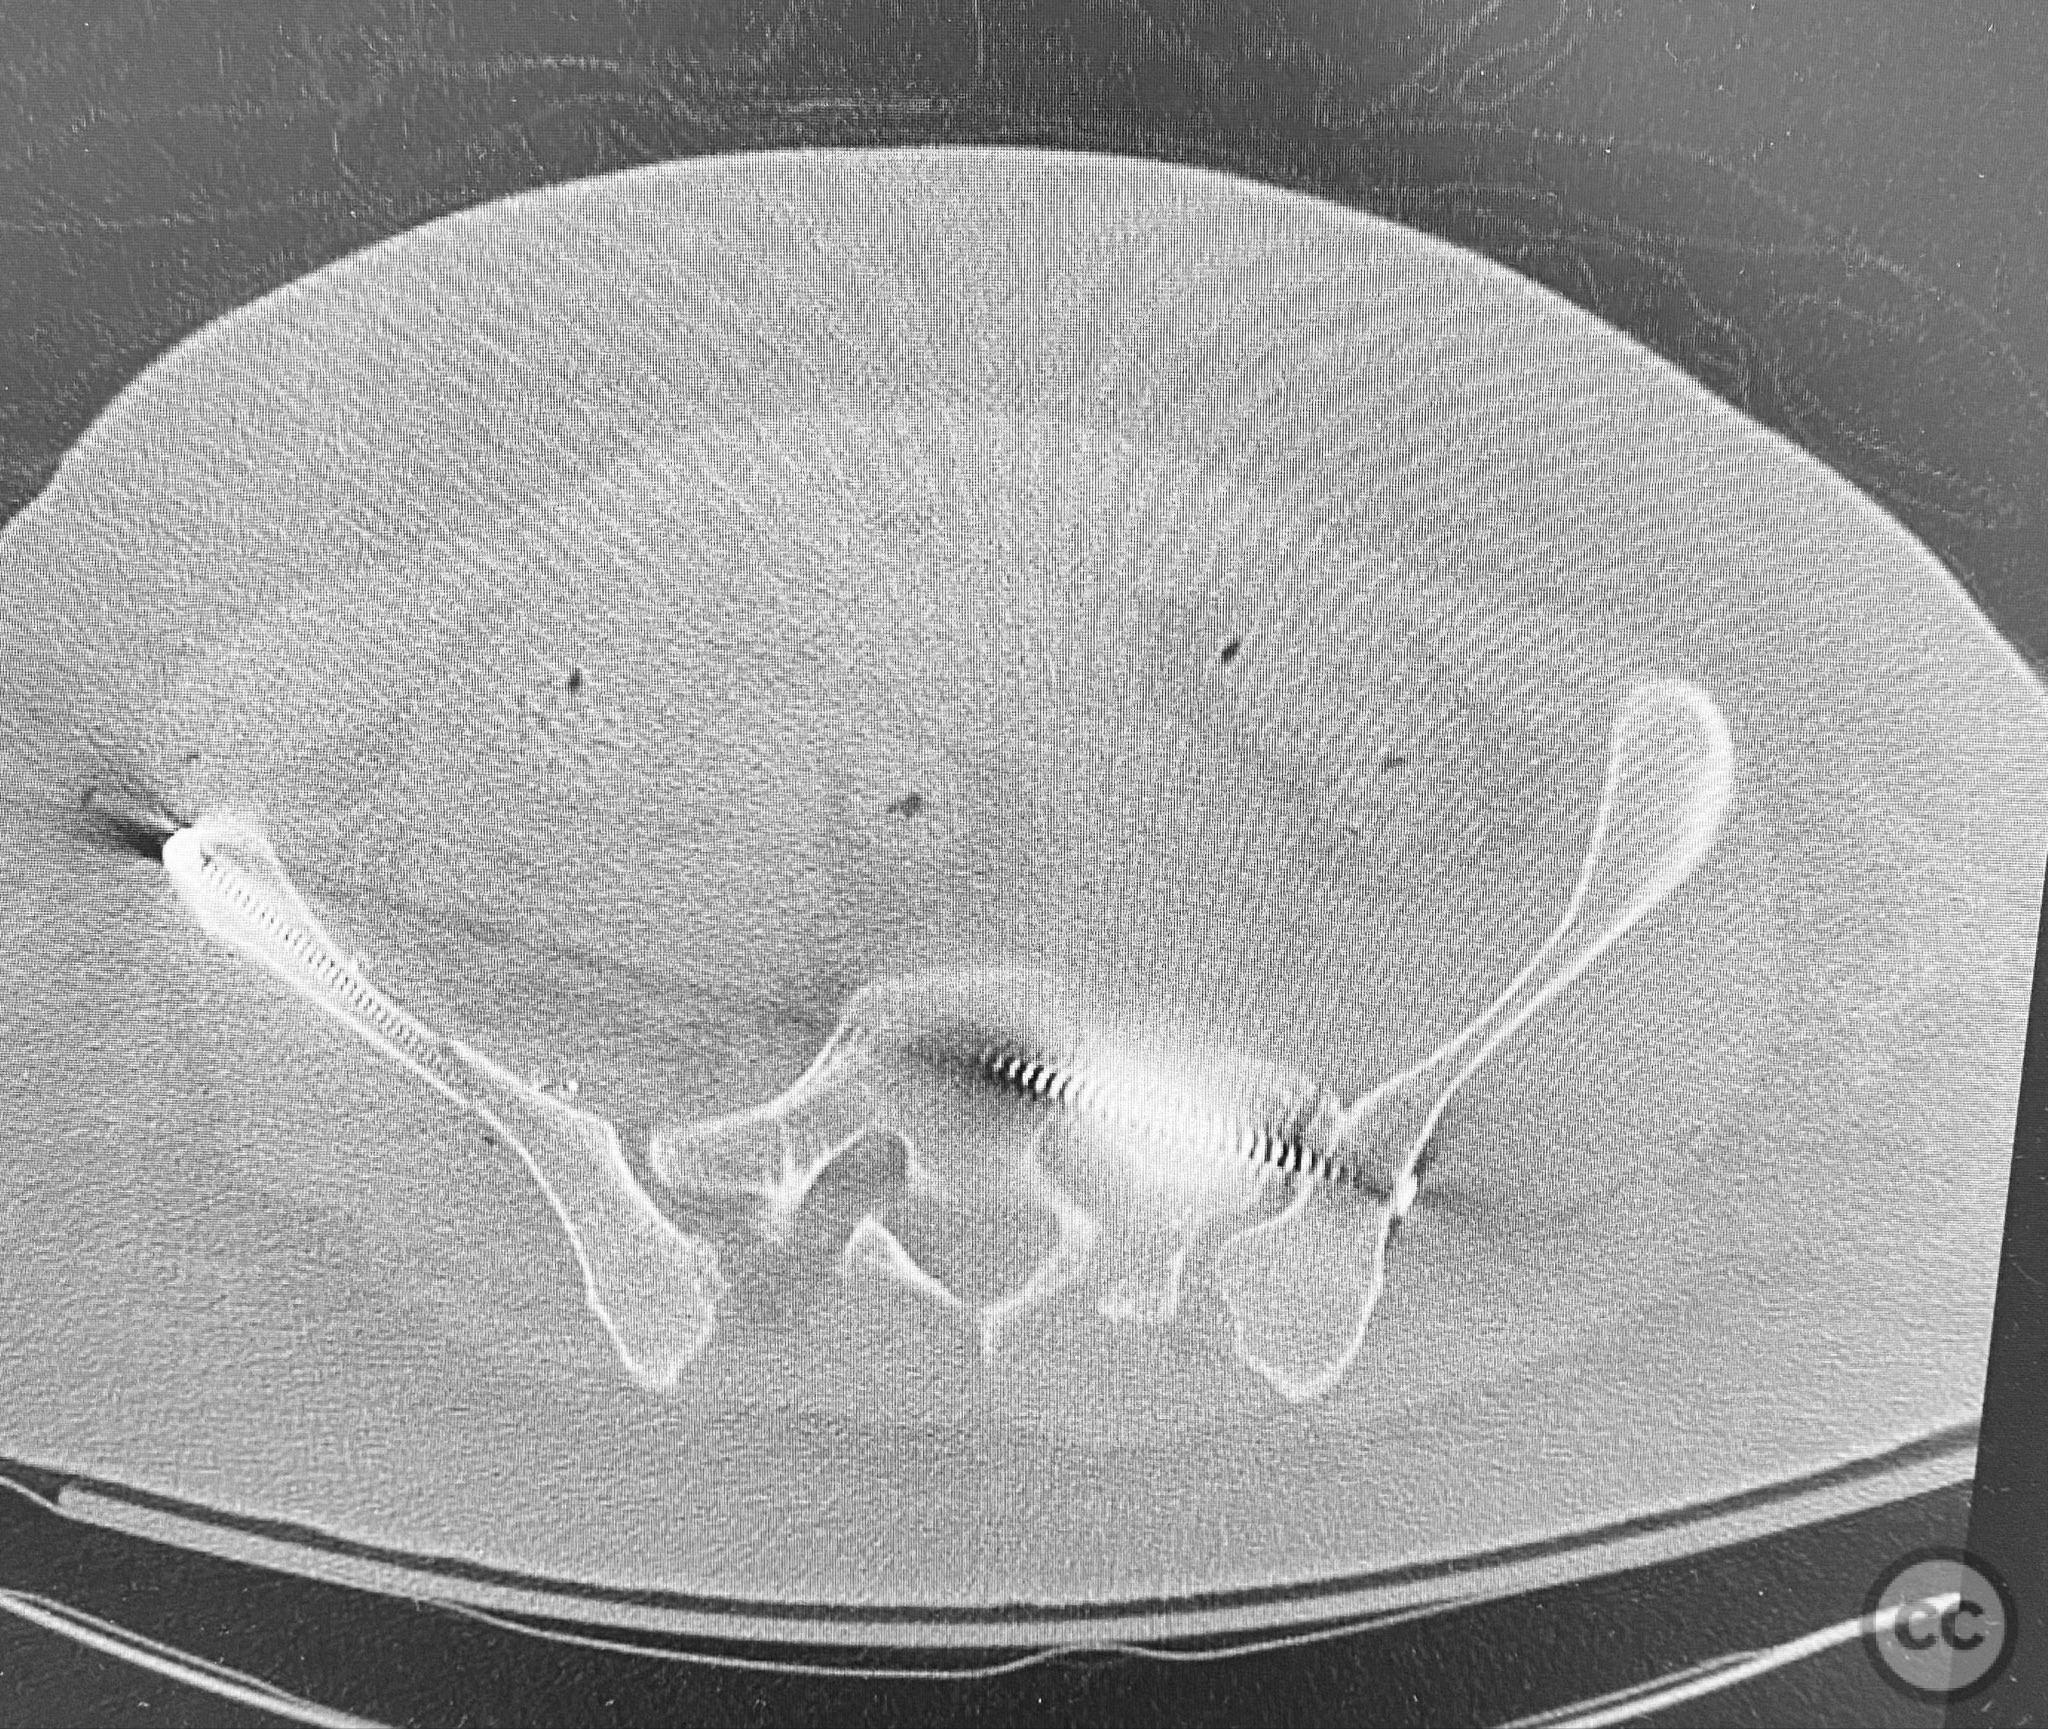

Clinical and radiological findings:  The patient presented following trauma with an unusual, significantly displaced right iliac fracture, accompanied by left-sided sacral and parasymphyseal ramus fractures. Initial AP pelvic radiography demonstrated the complex injury pattern. CT imaging provided detailed characterization of the iliac and sacral fractures, including assessment of displacement, bone quality, soft tissue status, and overall body habitus. No neurovascular compromise was reported. AO/OTA classification: Right iliac fracture 61B2.3 (partial unstable, lateral compression injury), left sacral fracture Denis zone I, left parasymphyseal ramus fracture.

Bilateral distal femoral traction resulted in excellent reduction of the sacral fracture but did not adequately reduce the iliac displacement. Percutaneous fixation of the sacrum was performed first, followed by open reduction of the iliac fracture. Intraoperative imaging confirmed that all implants were fully contained within the available osseous corridors, avoiding extraosseous penetration. The complexity of the iliac fracture required careful anatomical reduction and implant placement along the pelvic brim.

Orthopaedic implants used:   Pelvic brim contoured plate, cancellous screws, percutaneous sacral screw(s)